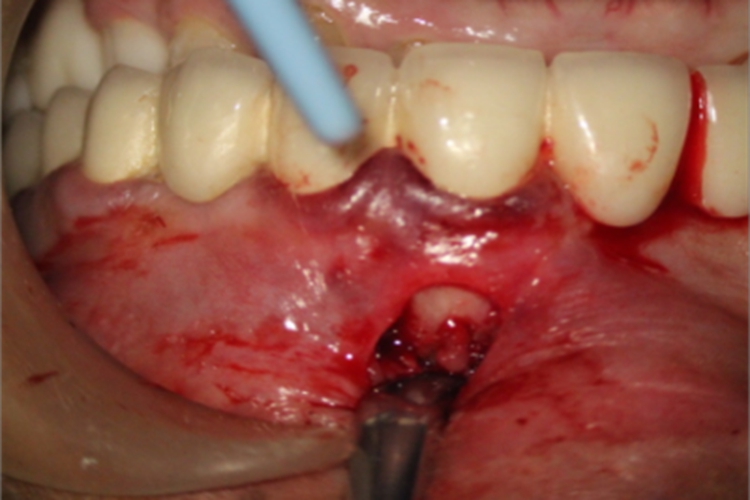

急性化脓性根尖周炎可表现为牙龈处出血、红肿,根尖周组织被切开,明显缺损,可见白色的牙根,患者自觉明显疼痛。

对于急性化脓性根尖周炎牙龈出血的情况,可由专业医生进行开窗减压术解除局部压力,因脓液局限在根尖周附近的牙周膜内,形成脓肿,切开根尖周组织后,血液和脓液流出,可以减轻局部疼痛,也能避免其向周边区域扩散。此外,需消除根尖炎症,患者可遵医嘱选择人工牛黄甲硝唑片、头孢克洛胶囊等药物控制根尖内的感染,然后进行根管治疗。医生会把病变位置的牙龈翻开,彻底刮除根尖脓肿。如果病牙不稳固,应一并拔除病牙。术后可遵医嘱口服对乙酰氨基酚片、双氯芬酸钠肠溶片等非甾体抗炎药物止痛。